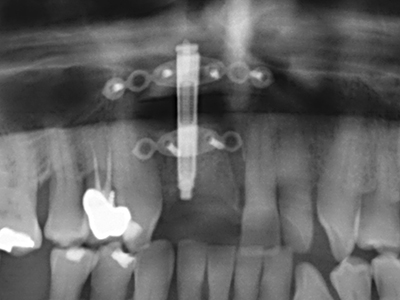

Bone tissue is not simply a mineral structure but also contains a substantial proportion of collagen fibres. This means it not only has good compressive strength but also a degree of flexibility, which can be taken advantage of when performing bone augmentations. In the classical expansion procedure using bone splitting, the atrophied alveolar ridge is split longitudinally and carefully expanded after reaching an adequate osteotomy depth (Fig. 13-16), ideally without substantial removal of the periosteum (Brugnami, Caiazzo et al. 2014, Stricker, Fleiner et al. 2014). Screw and plate systems with increasing expansion distance have proven effective in separating the two bone lamellae while remaining below the fracture threshold. In general, residual bone widths of at least 3–4 mm are required (Chiapasco, Zaniboni et al. 2006) to guarantee adequate flexibility and sufficient bone coverage of the future implants. If necessary, a vertical relief osteotomy on one or both sides can improve flexibility. A combination with additional augmentation techniques, particularly on the buccal side, has been described as an alternative to the classical technique.

The splitting procedure is particularly atraumatic and there is no significant loss of dimension when using piezosaws, and there are no significant differences between implants in split jaws and implants in an alveolar ridge without a bone deficit (Chiapasco, Zaniboni et al. 2006, Danza, Guidi et al. 2009). However, sufficient continuous irrigation is essential, particularly with locally restricted and deep splitting to prevent thermal stress in the apical osteotomy regions.